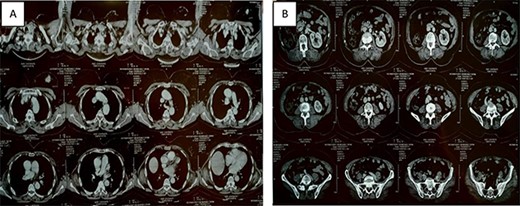

Thoracic-abdominal and pelvic computed tomography (CT) images showing on the thoracic level (A) a poorly limited mass measuring 27 × 22mm in the upper outer quadrant of the left breast (B) and a single left kidney at the abdomino-pelvic level.